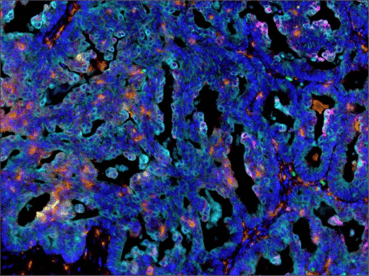

Multiplex IHC analysis of paraffin-embedded human ovarian carcinoma using CD68 (D4B9C) rabbit Monoclonal Antibody #76437 (orange), PD-L1 (E1L3N®) Rabbit Monoclonal Antibody #13684 (red), PD-L2 (D7U8C™) Rabbit Monoclonal Antibody (magenta) #82723, Arginase-1 (D4E3M™) Rabbit Monoclonal Antibody #93668 (green), IDO (D5J4E™) Rabbit Monoclonal Antibody #86630 (yellow), and Pan-keratin (C11) Mouse Monoclonal Antibody #4545 (cyan). |